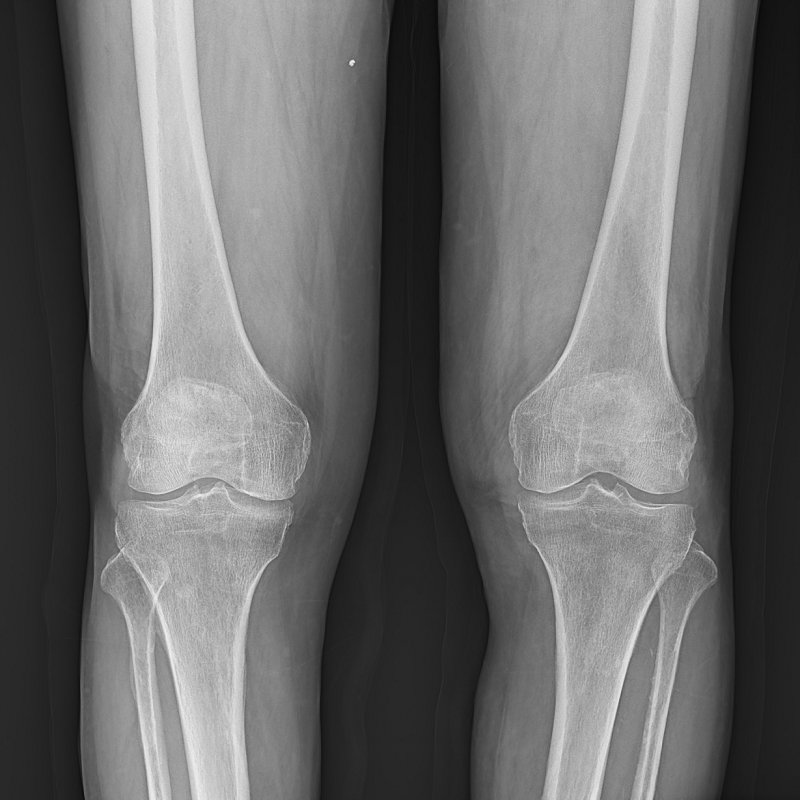

Clinical picture

臨床圖片